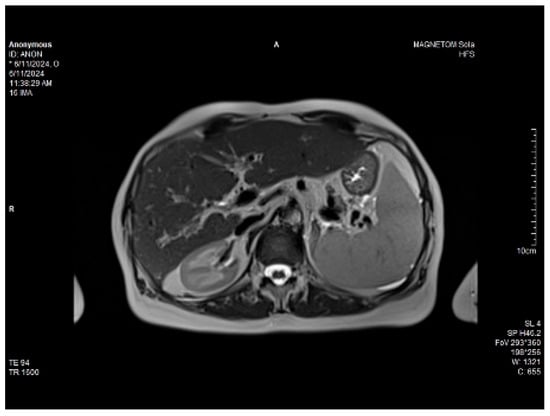

Abdominal MRI study confirmed the hepato-splenomegaly, ascites and the patency of the portal vein system. In addition, small veno-portal shunts were highlighted at the periphery of both hepatic lobes. Various MRI features are depicted in Figure 6, Figure 7, Figure 8 and Figure 9.

Figure 7. MRI: splenomegaly.